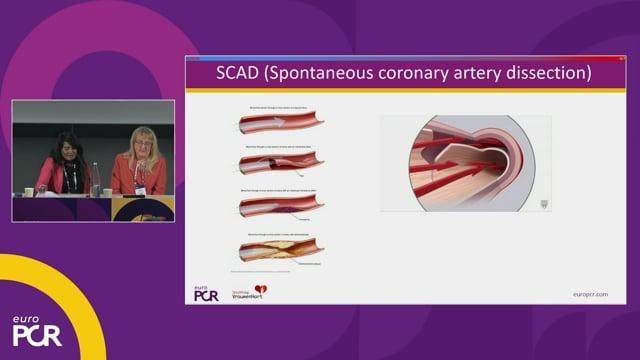

Beyond the diagnosis: a qualitative exploration of women’s experiences with cardiovascular disease

21 May 2026 – From EuroPCR 2026

This session presents a qualitative exploration of women's experiences with cardiovascular disease, highlighting unique challenges throughout their care pathway from diagnosis to rehabilitation. It shares robust patient experience data and offers recommendations aimed at improving cardiovascular care tailored to women’s specific needs.